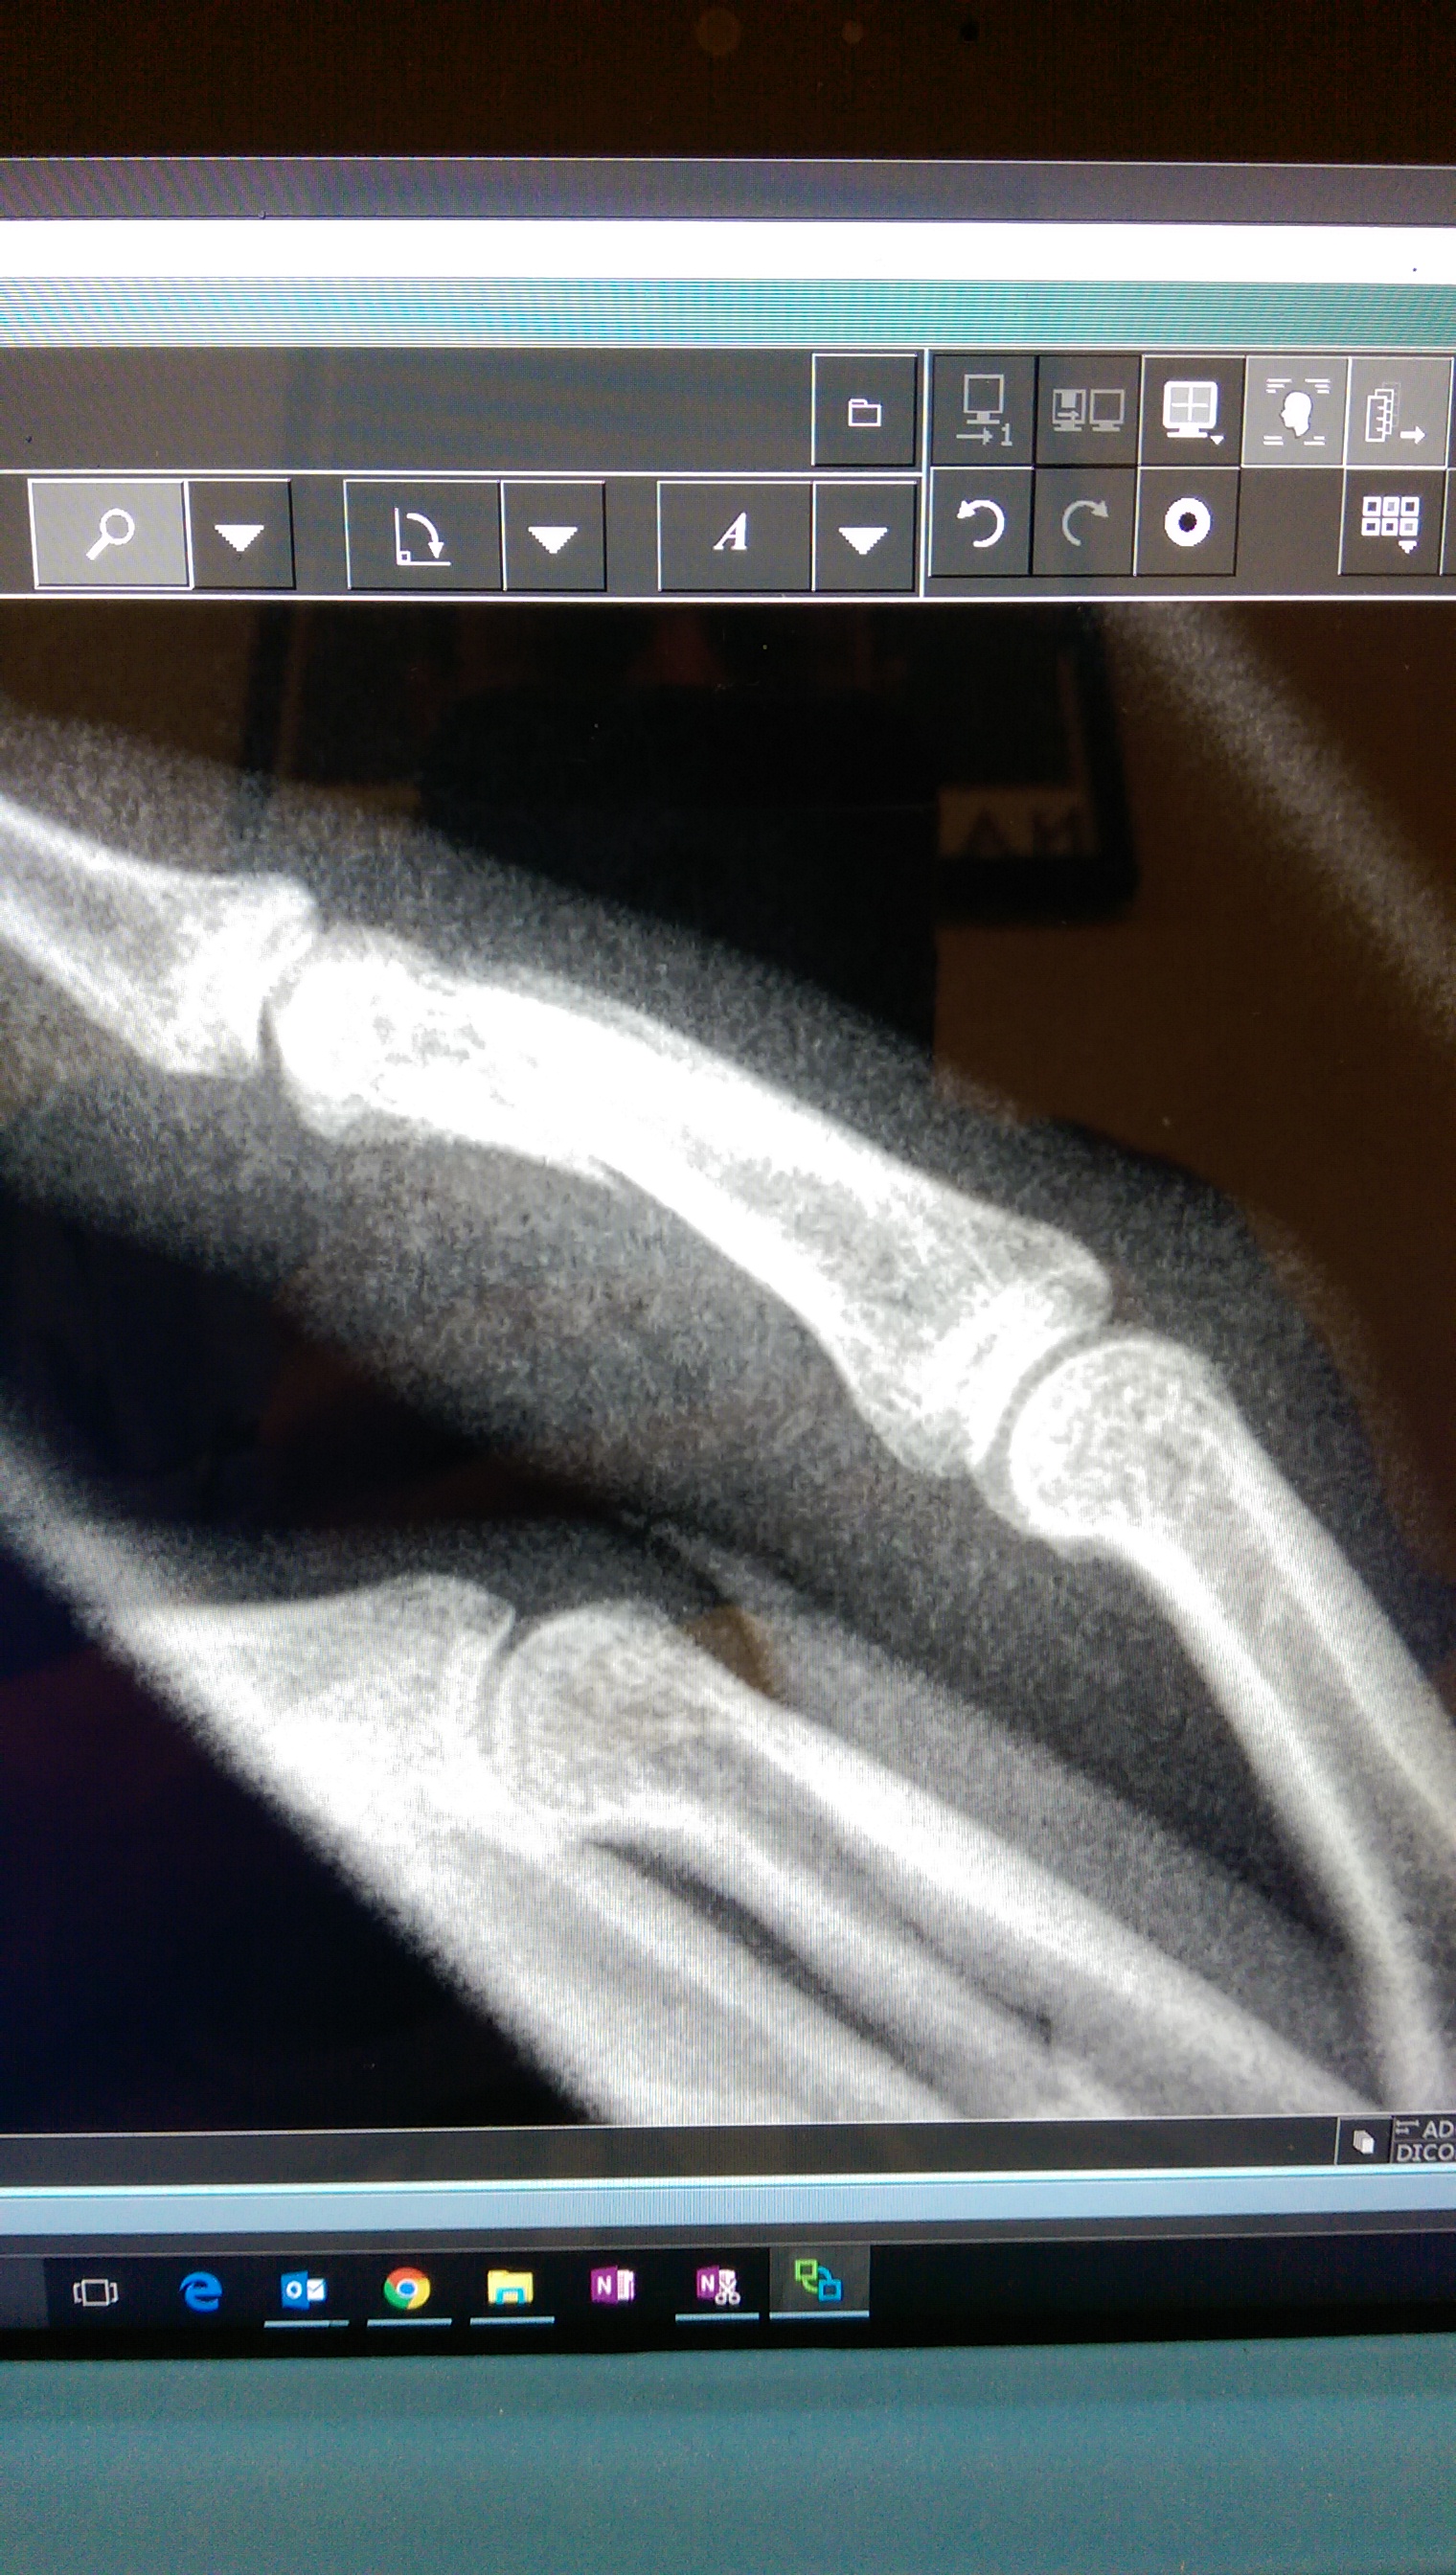

This is a “mildly comminuted and slightly displaced complete transverse fracture of the middle phalanx of the right 4th finger, with associated soft tissue swelling.” In translation I snapped my finger in half like a Q-tip.

Behold, an alternative view: